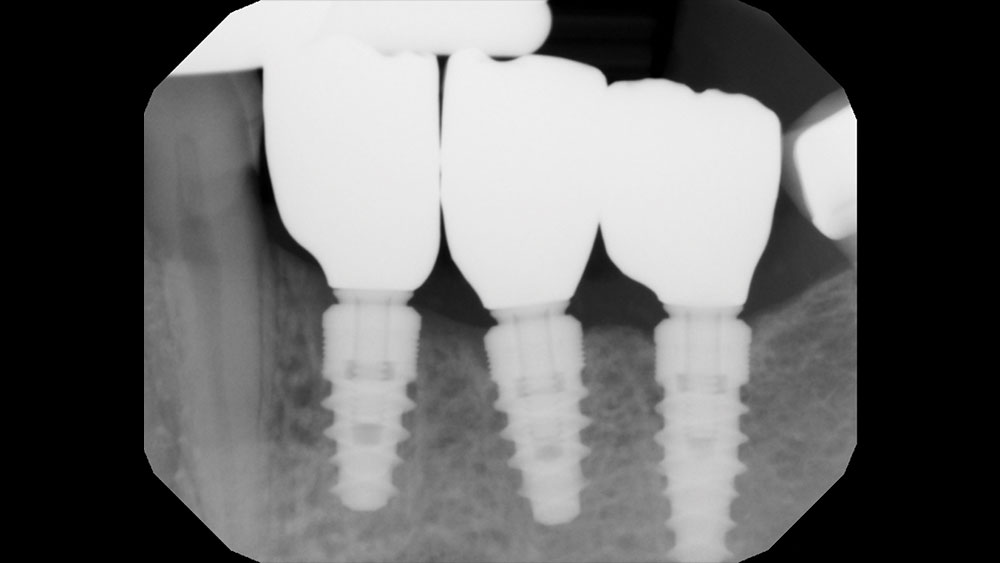

The patient selected implant treatment to replace her teeth. Screw-retained crowns were chosen instead of a cementable restoration, primarily due to the ease of retrievability afforded by screw retention. Because the posterior location of the restorations required resistance to occlusal forces as well as acceptable esthetics, I selected BruxZir® zirconia as the material; its high flexural strength and natural translucency fulfilled both requirements.

The question then became whether to use a splinted restoration in the form of a BruxZir screw-retained bridge, or unsplinted BruxZir screw-retained crowns. An assessment of this patient, as well as the pros and cons of both restoration types as previously outlined, led to the decision that an unsplinted restoration was the preferred treatment in this case. The key factors in this choice were as follows: